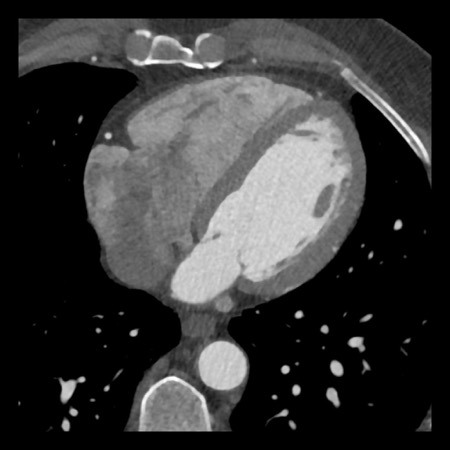

case 4 – CAD-RADS 3/P1/I+ thrombus left ventricle

First, scroll through the CTA images.

How would you describe the findings on the coronary CTA?

The findings are:

- Moderate (50-69%)

stenosis in the proximal LAD caused by a non-calcified plaque. - Variant of

sinoatrial (SA) nodal artery. The artery usually arises from the RCA as a second

branch after the conus artery, however in this case it arises from the LCX,

courses behind the aorta, anastomosing with the right atrium and with a small

branch supplies the SA-node of the heart. - Thrombus in the

apex of the left ventricle. - CTP was performed

in this patient. CTP showed a perfusion defect at stress imaging in the

territory of the LAD (I+), at rest no perfusion defect was visible.

This patient classifies as CAD-RADS 3/P1/I+, which means

this patient requires further investigation.